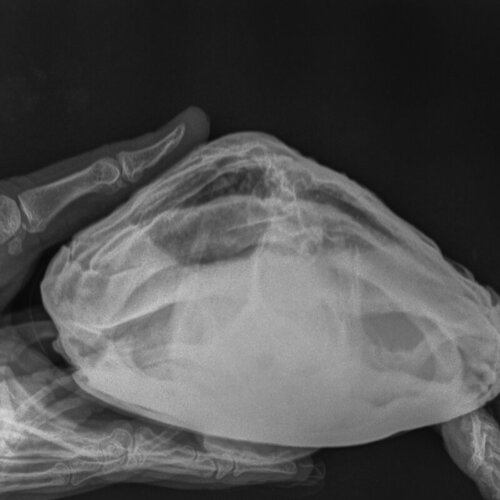

Обратились к местному ветеринару, сделали рентген, назначено лечение (кальций, байтрил, катобевит, раствор Рингера Локка). По снимкам ветеринар озвучил проблему с воспалением в легких и нарушением кладки яиц. Рекомендовано пару дней наблюдать и обратиться в СПб к герпетологу по вопросу оперирования (удаления яиц).

Хотелось бы понять насколько острая необходимость оперирования?

Мелкие животные_Рептилии-Череп DV_VD-08.10.2022-16_31_24-584.JPEG

Мелкие животные_Рептилии-Грудная клетка VD-08.10.2022-16_32_04-330.JPEG